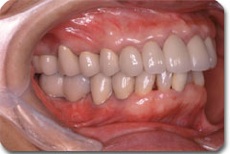

かみ合わせの改善を含めた総合的な治療により、このように崩壊したお口の中でも しっかり噛めて、美しい状態に治すことができます。この後は、定期的メインテナンスをお受けいただき、良い状態を守って行ければ長い期間、快適な食生活が営めるでしょう。どんな状態でも希望を持って、ご相談いただければ幸いです。

かみ合わせ治療によりここまで治すことができます